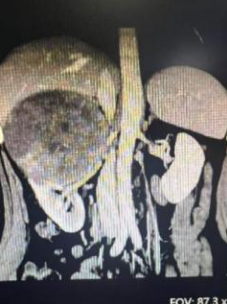

该患者因体检发现右肾占位入院,经进一步检查,被确诊为右肾恶性肿瘤。令人棘手的是,肿瘤体积巨大,直径长达13厘米,且位置特殊,与肾脏的重要流出血管——肾静脉以及毗邻的肝脏组织关系极为密切,界限不清。这极大地增加了手术的难度和风险,分离过程中稍有不慎,极易导致致命性大出血或损伤肝脏等重要器官,对主刀医生的经验、技术及团队配合都是严峻考验。

CT提示肿瘤13x10cm,紧邻肾静脉、十二指肠、肝脏等